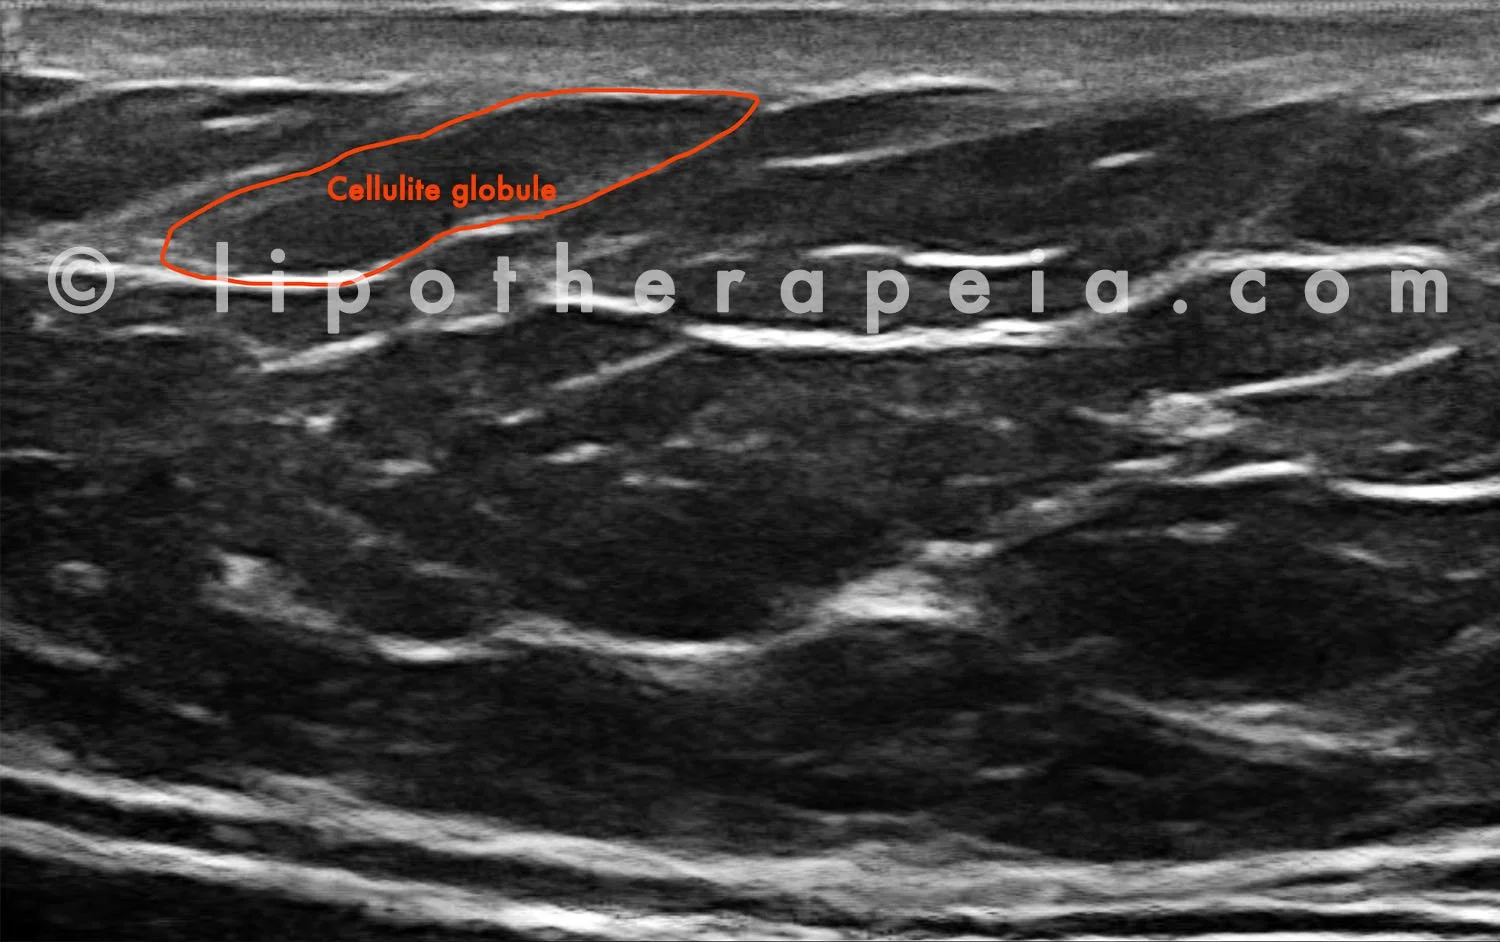

Thirdly, cellulite and fat look different with an ultrasound scan

With ultrasound cellulite reveals a honeycomb structure while fat that does not cause bumps or ridges reveals a much simpler pattern.